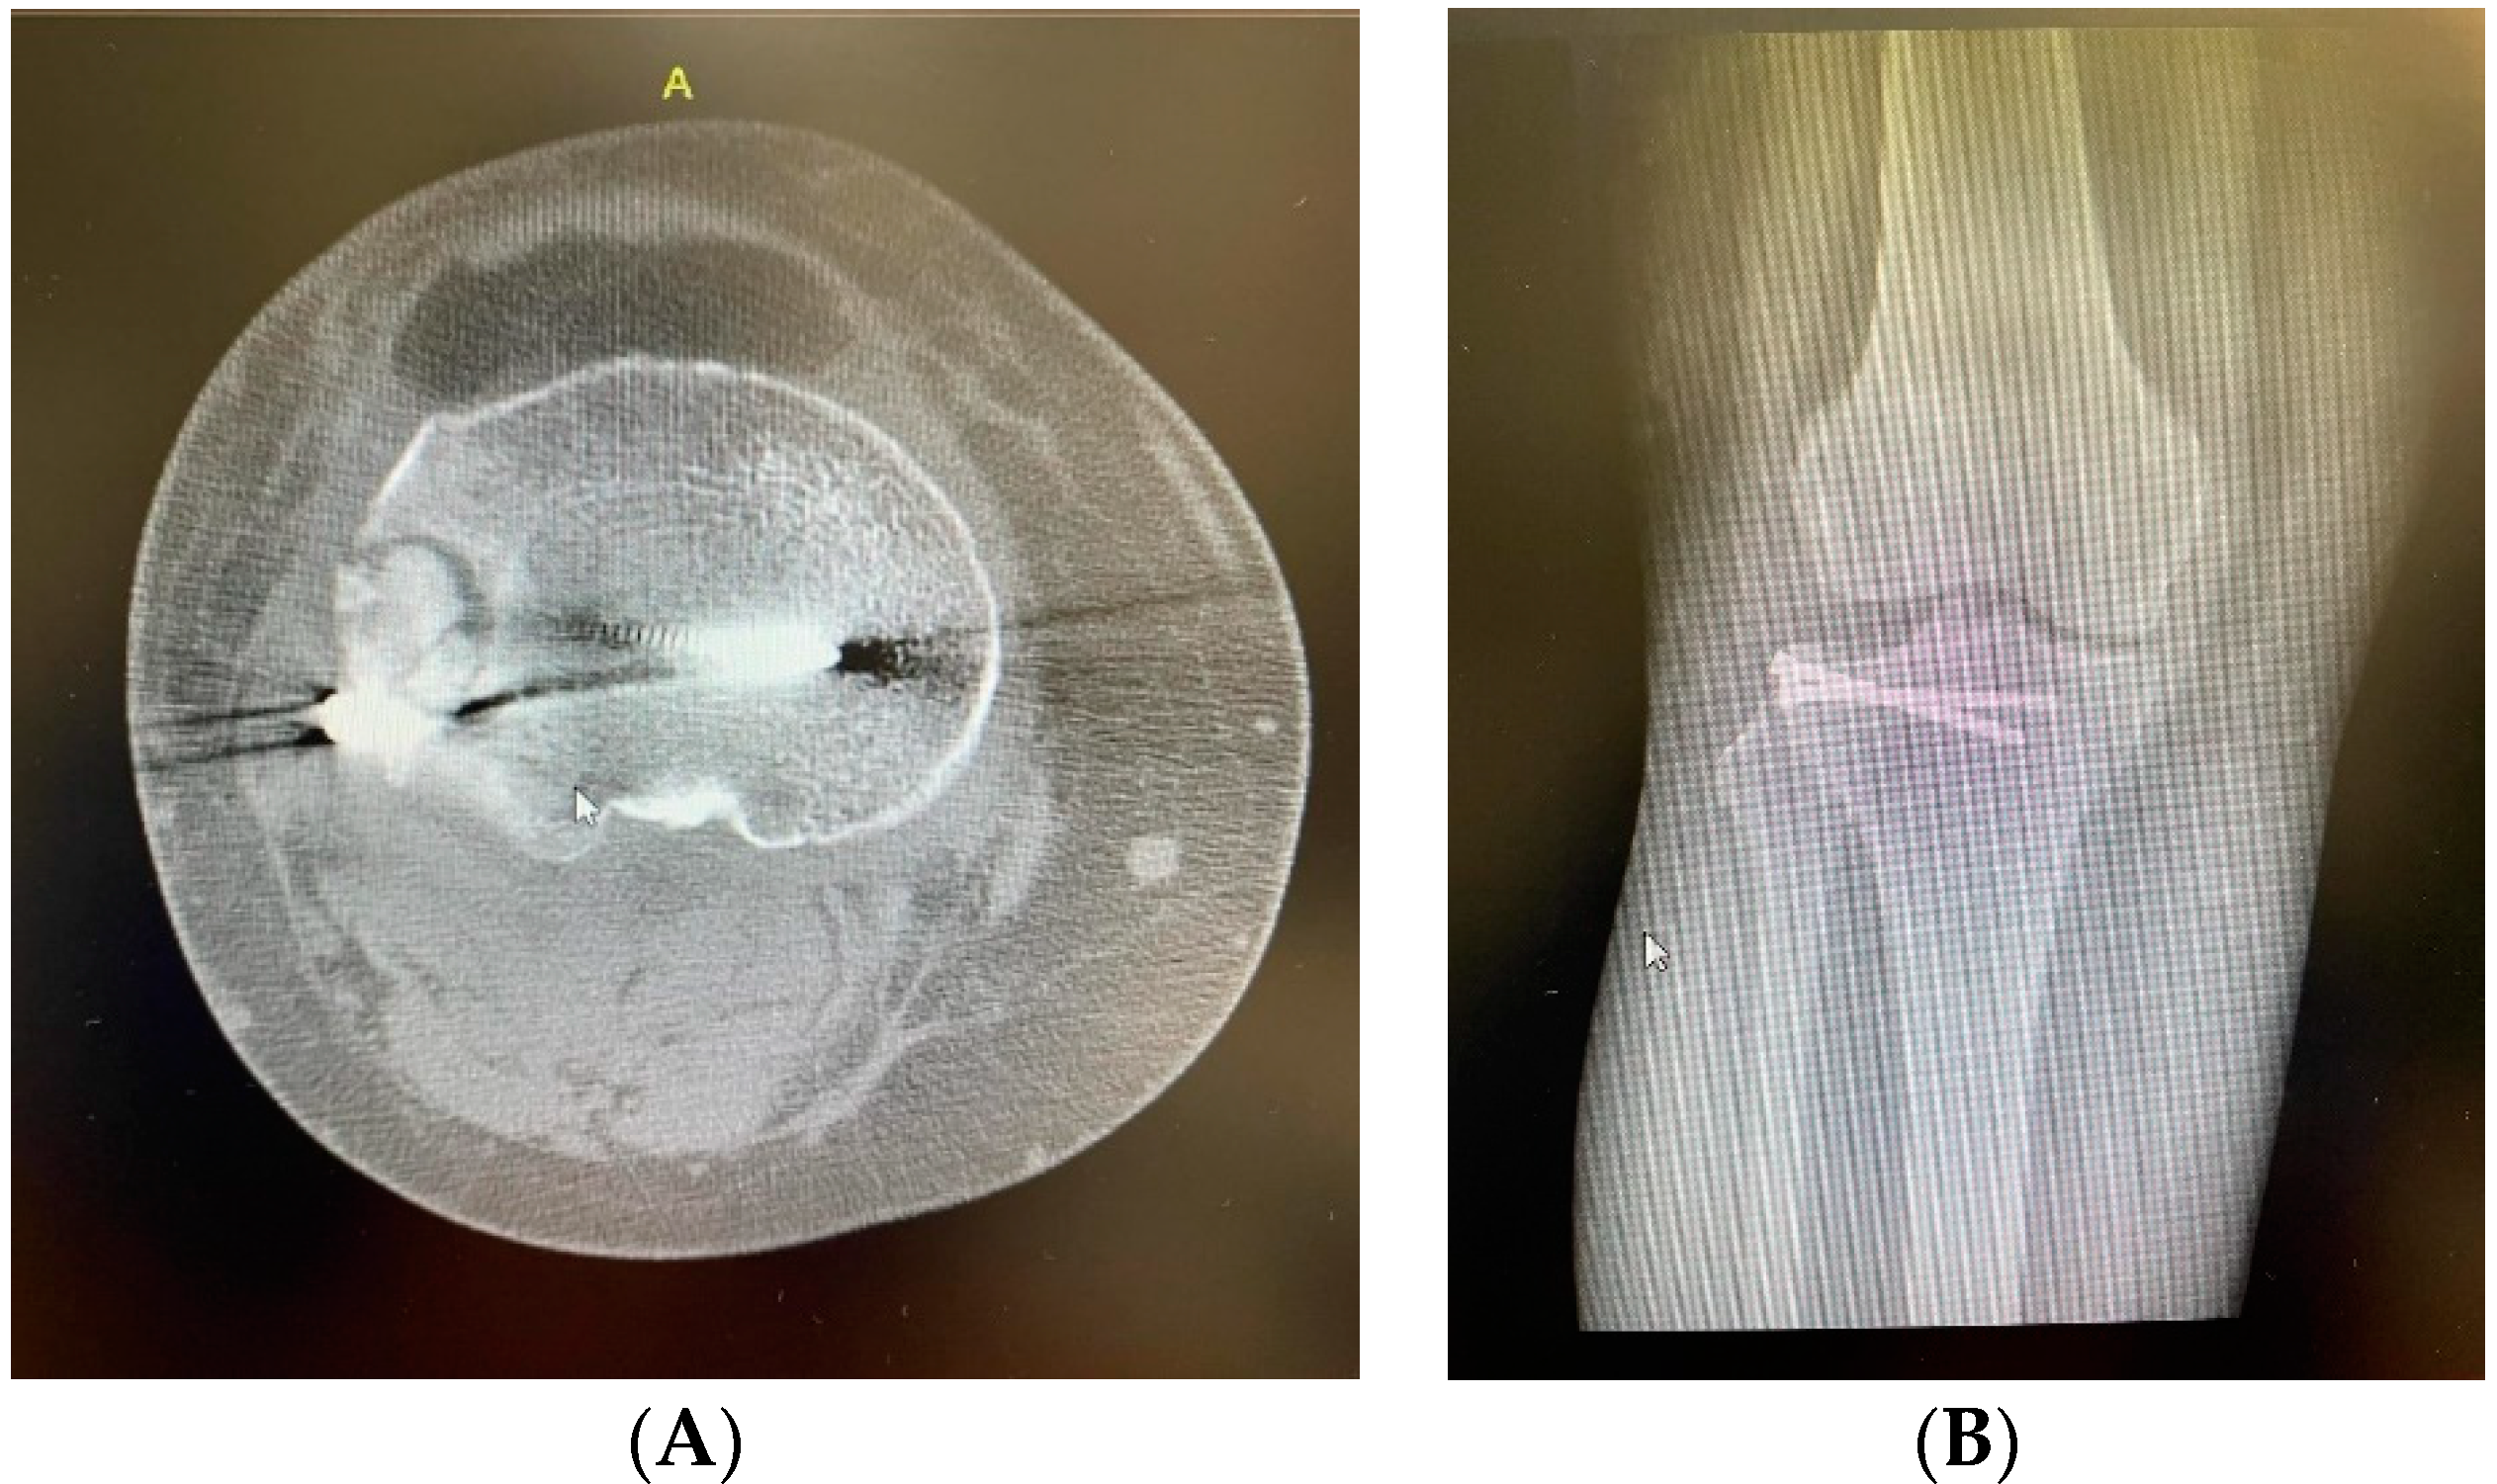

2. Clinical Case Presentation